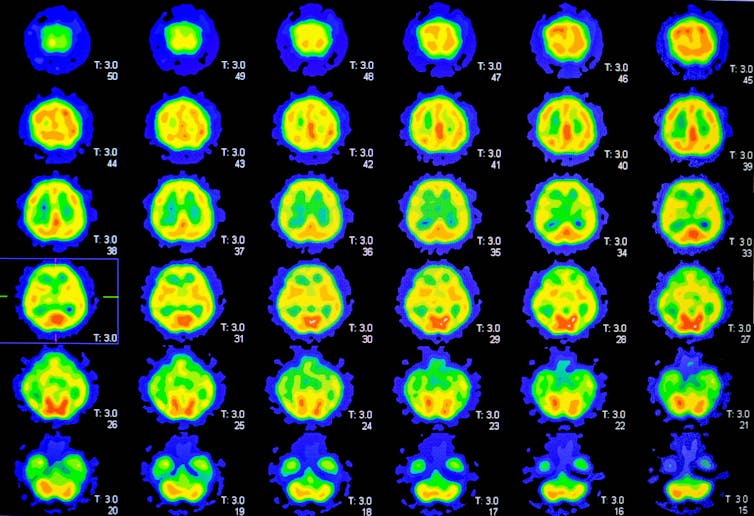

Positron emission tomography (PET) imaging was also used to scan their brains for markers of Alzheimer’s disease and determine their risk of developing it.

The researchers were mainly looking for the presence of amyloid plaques, which are one of two hallmarks of Alzheimer’s disease. These toxic amyloid plaques form when protein pieces, called beta-amyloid, clump together.